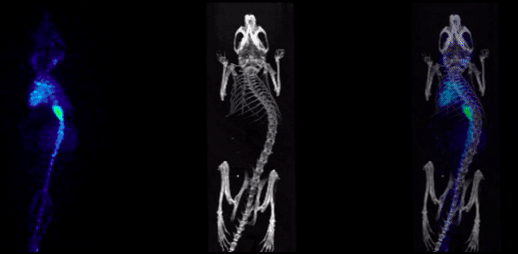

2、CT imaging combined with SPECT

SPECT/CT combination images, bone imaging of mice: 99mTc-HDP, 94.35MBq (2.55mCi) @start acquisition, acquisition time of 60min.